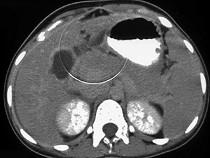

问题 女,45岁,急性右上腹剧痛2小时,向右肩放射,影像检查如图,应诊断为 ( )

选项 A.急性胆囊炎 B.慢性胆囊炎 C.胆囊穿孔 D.胆囊腺肌增生症 E.胆道梗阻

答案 C